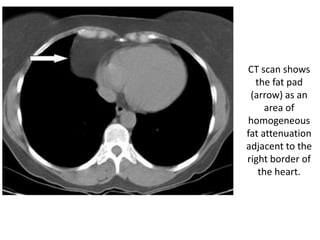

CT scan shows

the fat pad

(arrow) as an

area of

homogeneous

fat attenuation

adjacent to the

right border of

the heart.